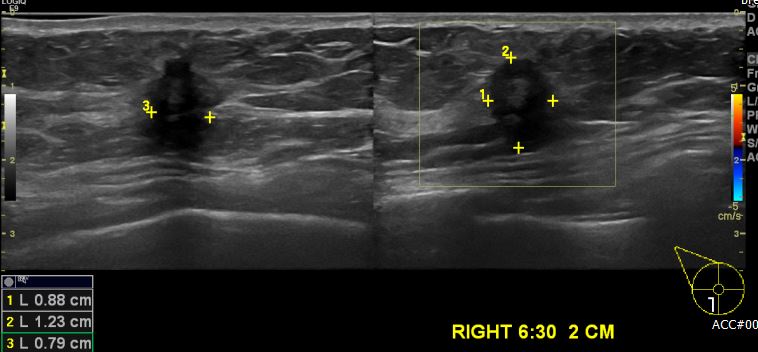

상기환자 건강검진상 이상 소견으로 내원하신 50대 여성 분으로 우측 6시30분 방향에서

2cm 떨어진 거리에 의심 스러운 혹 조직검사 시행햐여 우측 침윤성 유관암 진단 되었습니다.